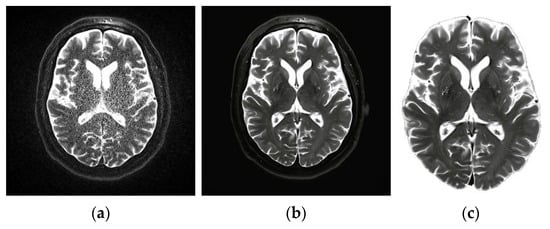

4.1.2. Pre-Processing

- Suhas, S.; Venugopal, C.R. MRI image preprocessing and noise removal technique using linear and nonlinear filters. In Proceedings of the 2017 International Conference on Electrical, Electronics, Communication, Computer, and Optimization Techniques (ICEECCOT), Mysuru, India, 15–16 December 2017; pp. 1–4. [Google Scholar]